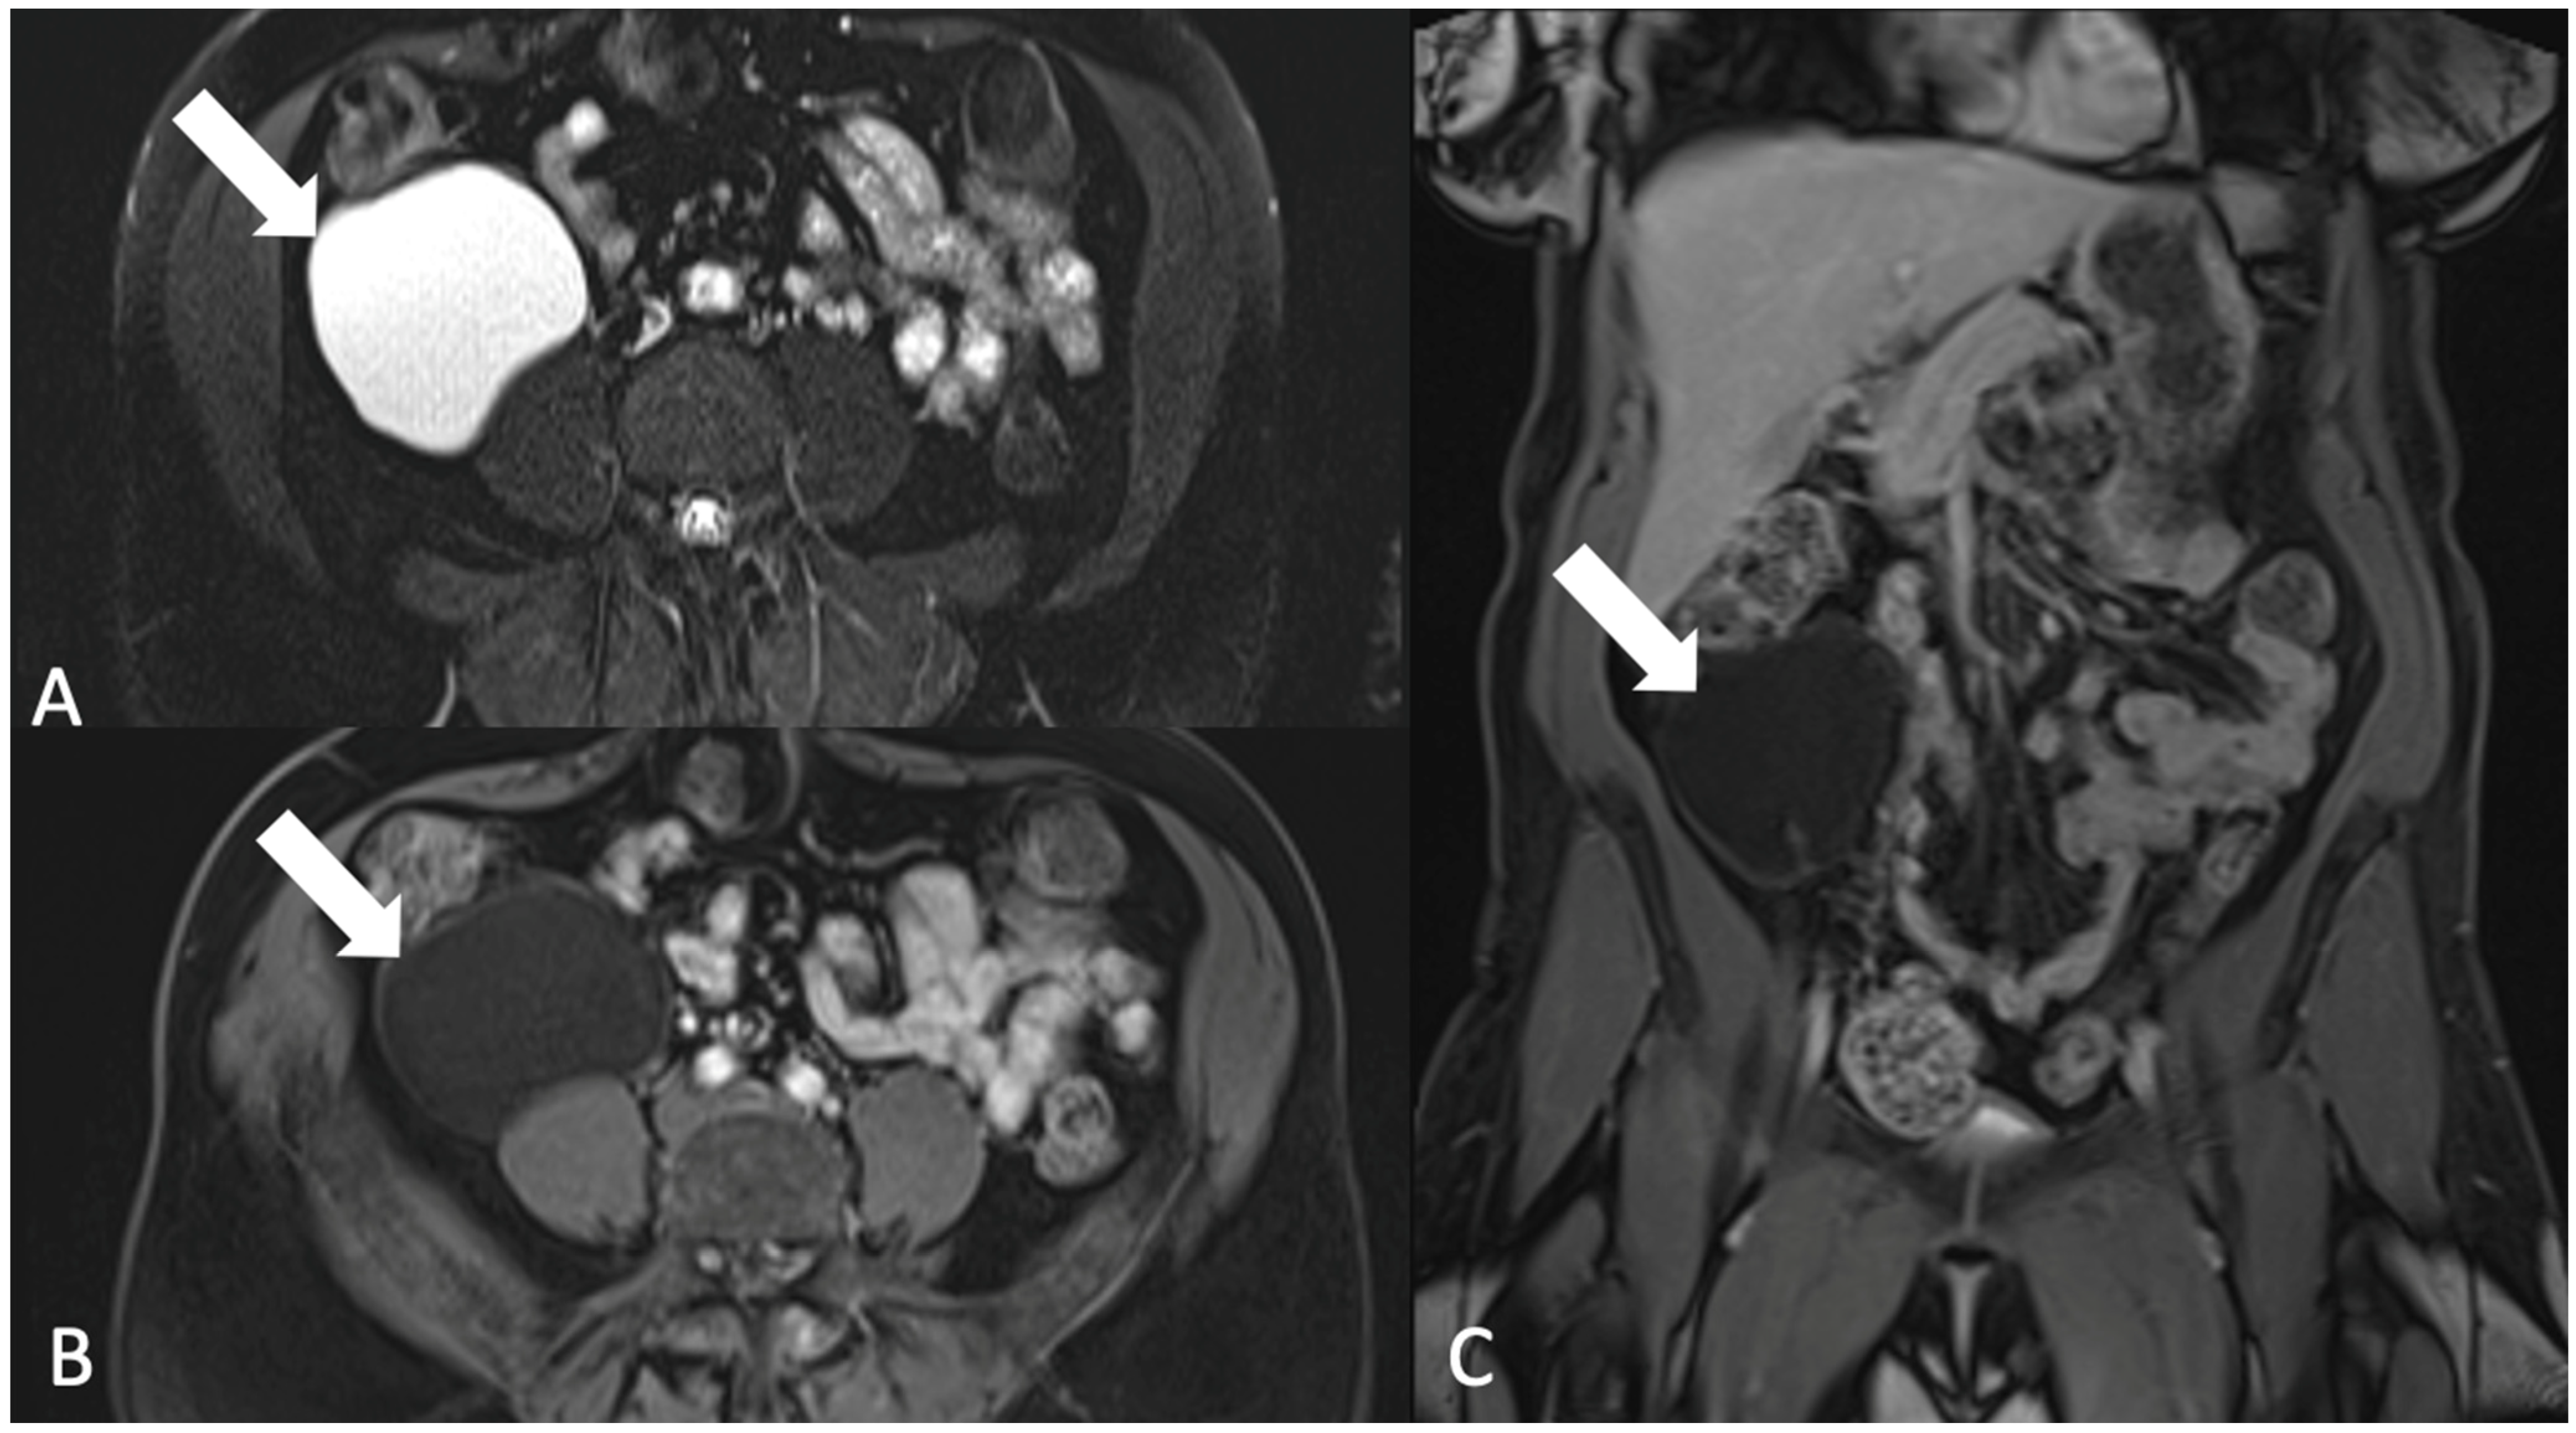

4. Imaging

5.4. Gastrointestinal Lesions

5.4.3. Gastrointestinal Stromal Tumor (GIST)